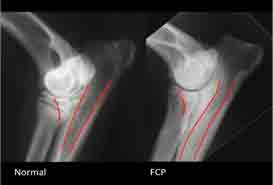

Also known as a “Floating Kneecap”. What happens here is the patella (Kneecap) will dislocate and slide out of its normal position by moving the patella from side to side instead of up and down. This happens as the grove in which the patella sits is too shallow. Luxation Patella is caused by breeding and genetics of the dog, malformation during the growth phase in a puppy and trauma to the knee i.e. a dog who’s home consists of laminate flooring (Slippy flooring).